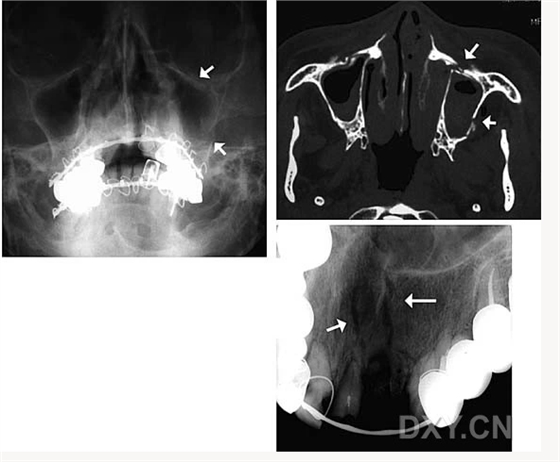

鼻鄂囊腫